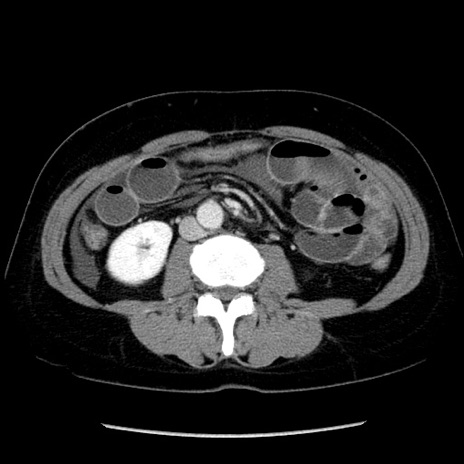

症例6(横断像)

【症例】50歳代女性

【主訴】下腹部痛

【現病歴】本日朝より下痢2回あり。 昼食を食べた後、嘔吐3回、下腹部痛認め、症状軽快せず、当院救急搬送。

最終食事:本日昼(生ものなし)。 昨日の夜、刺身を食ぺたとのこと。周囲に同様の症状の者なし。普段、排便は毎日あるとのこと。

【既往歴】卵巣癌術後(8年前に当院で卵巣摘出)

【身体所見】 意識清明、腹部:平坦、腸蠕動音→、やや硬、下腹部自発痛・圧痛あり、反跳痛あり、筋性防御なし。

【データ】WBC 16000、CRP 0.01